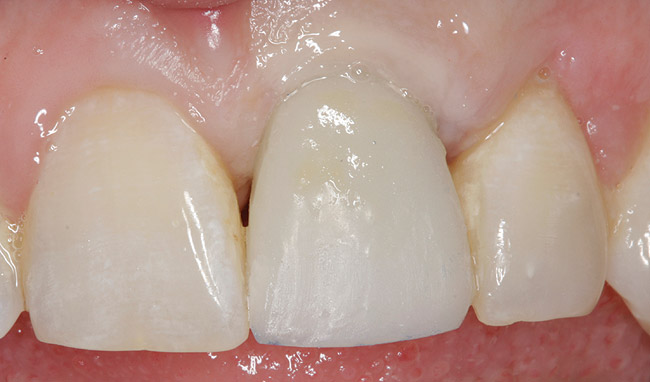

Achieving outstanding esthetics with implant dentistry is a reality (Figure 11 and Figure 12). Restorative efforts require disciplined steps to attain predictable results. To paraphrase my mentor, Cary Shapoff, DDS, renowned for his knowledge of periodontal disease treatment, bone grafting procedures, and dental implant surgery, implant esthetics is a series of well-planned, well-executed small steps that add up to a successfully restored fixture.

Fig 11. Preoperative photograph.

Figure 11